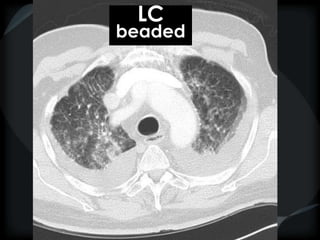

Septal Pattern – lymphatic/venous

● Beaded – lymphangitic carcinomatosis, lymphoma,

beaded